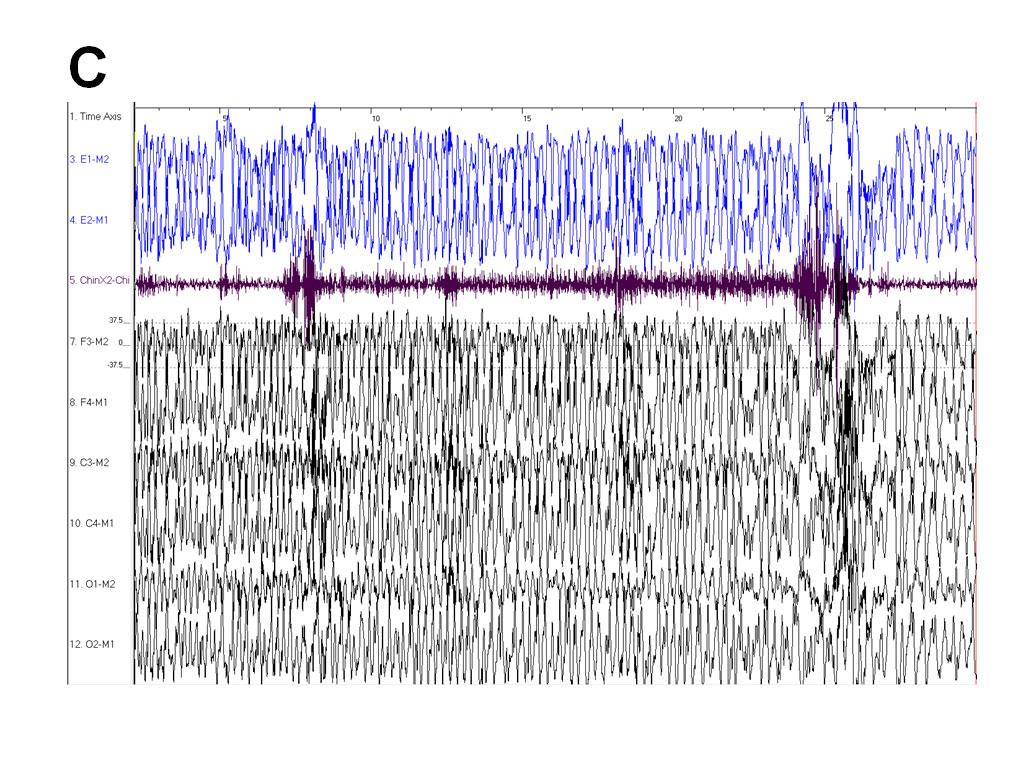

QUESTION 2: What do Epochs (B to D) represent in terms of EEG activity?

Answer 2: Subclinical ictal epileptiform activity.

Localized ictal epileptiform activity is also known as electrographic seizure activity. It usually persists for more than several seconds, begins abruptly (see Epoch B and F), and consists of repetitive and rhythmic waveforms that tend to vary in form, frequency and topography through out the seizure (see Epoch B-D and F). Epoch F shows ictal epileptiform activity at standard EEG rates of 30mm/sec. In our patient, tonic-clonic activity was not noted on video monitoring, although there was increase in chin EMG tone (see Epoch C). Ictal EEG patterns that occur in the absence of clinical seizure manifestations are referred to as subclinical ictal or subclinical electrographic seizure activity. Our patient was in NREM sleep during these discharges. Seizures are more common in NREM sleep than in wakefulness or REM sleep but are often subclinical (1). Our patient was subsequently referred for a formal electroencephalogram which confirmed subclinical epileptic activity.